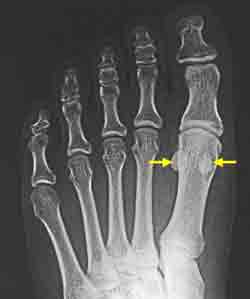

正常的籽骨形態拇外翻的籽骨形態籽骨分裂或二分籽骨如果足底軟組織較少或者穿著高跟鞋、薄底鞋等,這個部位也會出現疼痛。大腳趾向小趾方向偏斜時,前腳掌容易變寬,第二腳趾下方易出現疼痛和老繭,同時籽骨也會向小趾方向移動,當體重集中在這個部位時,出現疼痛就不奇怪了。有先天性和後天性之分,通過X線照片比較難區別,誤診和漏診率較高。

除了晚期患者之外,X-線照片檢查對籽骨炎診斷幾無價值;X-線斷層照片檢查有助於勾勒骨改變的輪廓,而三相骨掃描檢查可證實關節區域的同位素陽性攝取。